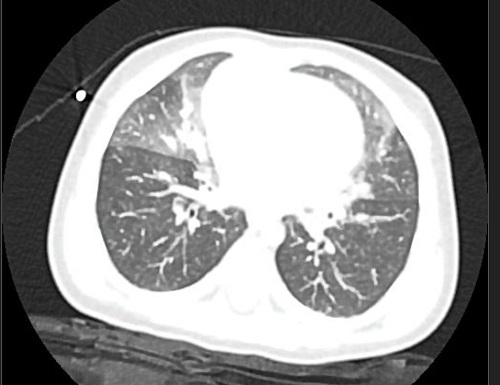

Se deriva a de nuevo a Neumología, donde se realiza TAC pulmonar, con el diagnóstico de HNE (Figuras 1 y 2).

Figura 2. Opacidades en vidrio esmerilado en TAC pulmonar

Las patologías intersticiales difusas pulmonares son un grupo de enfermedades raras que pueden inicialmente confundirse con otros cuadros respiratorios de mayor prevalencia, al ser su presentación inespecífica, siendo un reto para los pediatras.  Las células neuroendocrinas (derivadas del endodermo) se acumulan en el intersticio pulmonar de los lactantes con diagnóstico de HNE y secretan en el árbol bronquial histamina y el péptido liberador de gastrina, bombesina. La HNE suele acompañarse de hipoxemia crónica, retracciones intercostales, subcostales y subcrepitantes. No presenta tos ni estornudos. La radiografía de tórax puede ser normal o con signos de hiperinsuflación. El mejor método de imagen no invasivo es la TAC, cuyos hallazgos ─opacidades en vidrio esmerilado, en el lóbulo medio y la língula, así como los segmentos mediales del lóbulo superior e inferior─ son suficientes para realizar el diagnóstico. Se han descrito presentaciones atípicas de HNE, donde la TAC no es suficiente y se llega a una biopsia pulmonar. No existe un tratamiento específico y la pobre respuesta a los corticoides confirma el diagnóstico. El manejo consiste en dar soporte y cuidado preventivo: oxigenoterapia, soporte nutricional y tratamiento del reflujo gastroesofágico. No existen reportes de muertes, la evolución es crónica, pero con tendencia a la curación espontánea en meses o años.